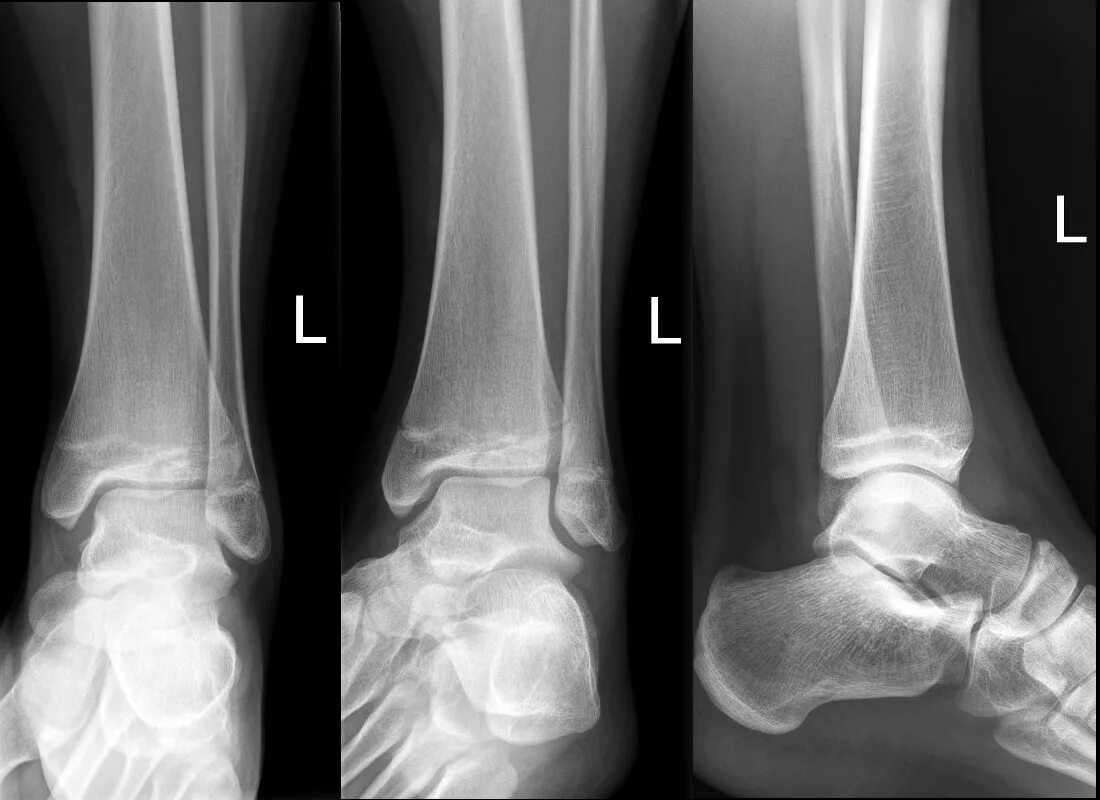

Fracture modeling